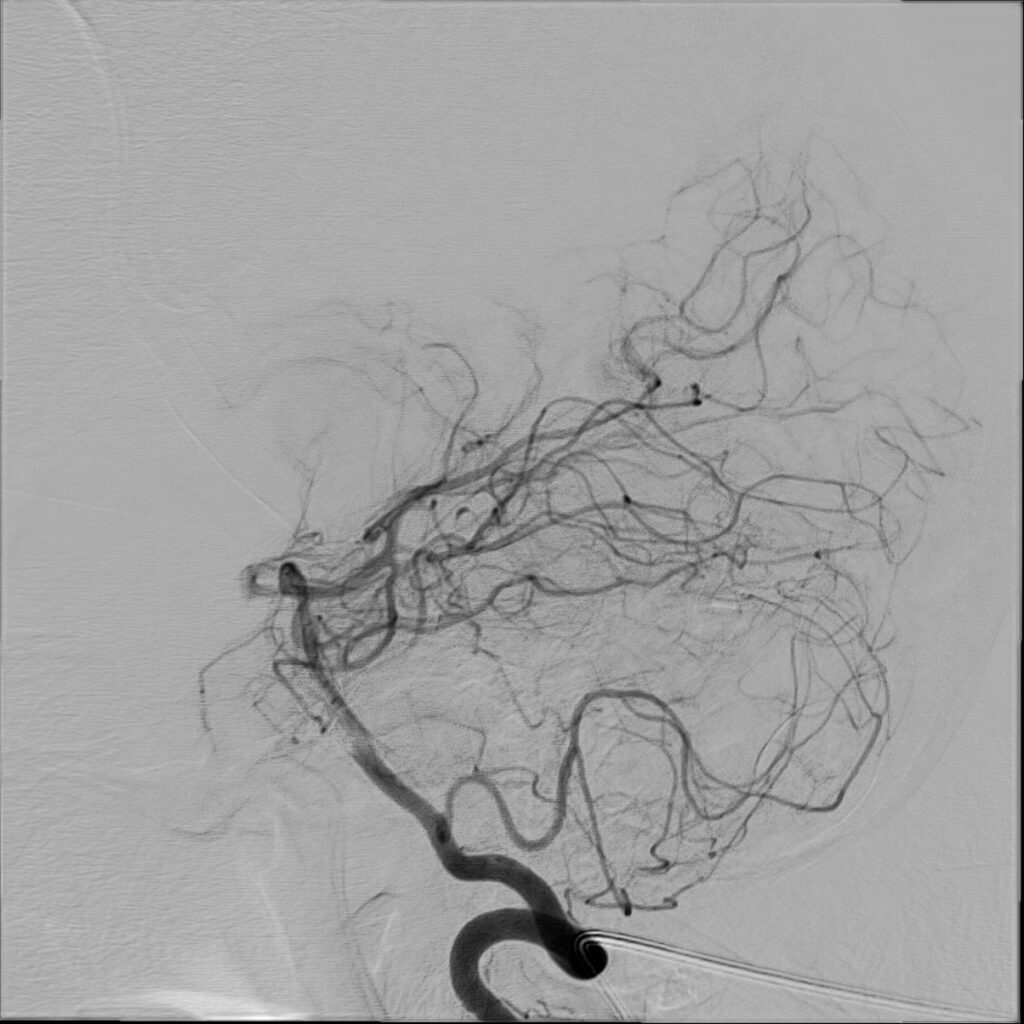

W badaniu CT widoczne jest rozległe krwawienie dokomorowe.

W badaniu angiografii subtrakcyjnej widoczne jest rozległe (ponad 3 cm) gniazdo naczyniowe zaopatrywane z tętnicy przedniej mózgu prawej, zarówno z gałęzi okołospoidołowej, która oddawała 2 tętnice żywiące, jak i gałęzi korowych, oddając jedno naczynie żylne drenujące do zatoki strzałkowej górnej.

W tym przypadku chora została zakwalifikowana do leczenia operacyjnego – kraniotomii czołowej przystrzałkowej i resekcji zmiany naczyniowej. Zmiana została usunięta, bez nowych deficytów neurologicznych. W kontrolnym badaniu DSA nie uwidoczniono resztkowej przetoki naczyniowej, co jest sukcesem operacyjnym.